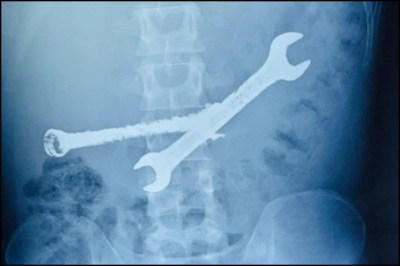

Jaipur Doctors Remove Toothbrushes And Iron Wrenches: युवक के पेट के भीतर कोई मामूली पत्थर नहीं, बल्कि 7 टूथब्रश और 2 लोहे के पाने (स्पैनर) मौजूद थे।

X-ray pic

Jaipur Doctors News: राजस्थान की राजधानी में एक ऐसा मामला सामने आया है जिसे सुनकर आपकी रूह कांप जाएगी। जयपुर के निजी अस्पताल में डॉक्टरों ने एक 26 साल के युवक के पेट का ऑपरेशन कर जो सामान बाहर निकाला, उसने मेडिकल टीम को भी हैरत में डाल दिया। युवक के पेट के भीतर कोई मामूली पत्थर नहीं, बल्कि 7 टूथब्रश और 2 लोहे के पाने (स्पैनर) मौजूद थे।

वरिष्ठ गैस्ट्रो सर्जन ने बताया कि भीलवाड़ा का रहने वाला यह युवक असहनीय पेट दर्द की शिकायत लेकर आया था। जब एंडोस्कोपी की गई, तो मॉनिटर पर दिख रही तस्वीरों ने सबको चौंका दिया। पेट के अंदर लोहे के औजार और प्लास्टिक के ब्रश आमाशय की दीवार को छलनी करने ही वाले थे।

डॉक्टर्स के मुताबिक, वस्तुएं इतनी नुकीली और सख्त थीं कि उन्हें एंडोस्कोपी (मुंह के रास्ते) से निकालना जानलेवा हो सकता था। ऐसे में टीम ने तुरंत ओपन सर्जरी का फैसला लिया। घंटों चली मशक्कत के बाद एक-एक कर सात ब्रश और दो भारी लोहे के पाने बाहर निकाले गए।